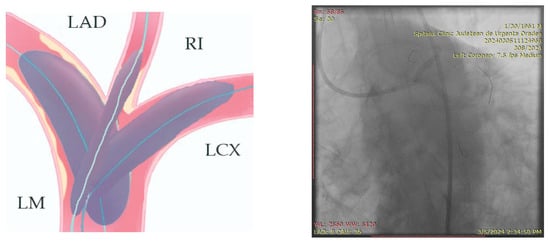

- Engage the left coronary artery with an EBU 4.0/8F guiding catheter. Wiring the three branches of the trifurcation (Floppy guide wires in LAD and RI, Hydrophilic guide wire in LCX) (Figure 14).